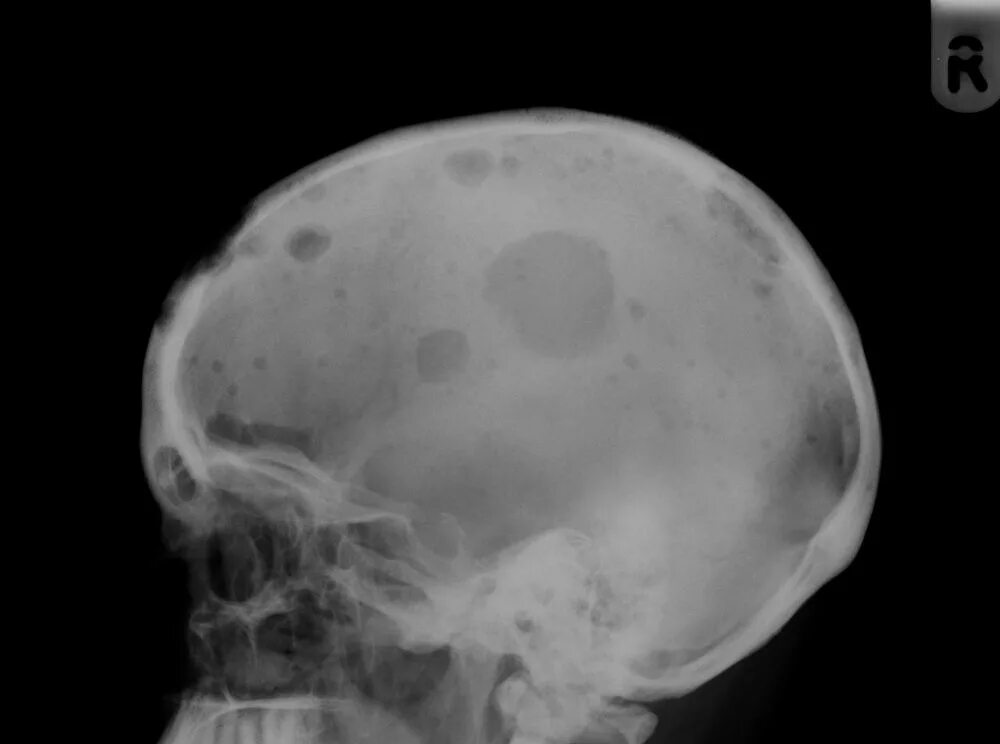

Метастазы в костном мозге